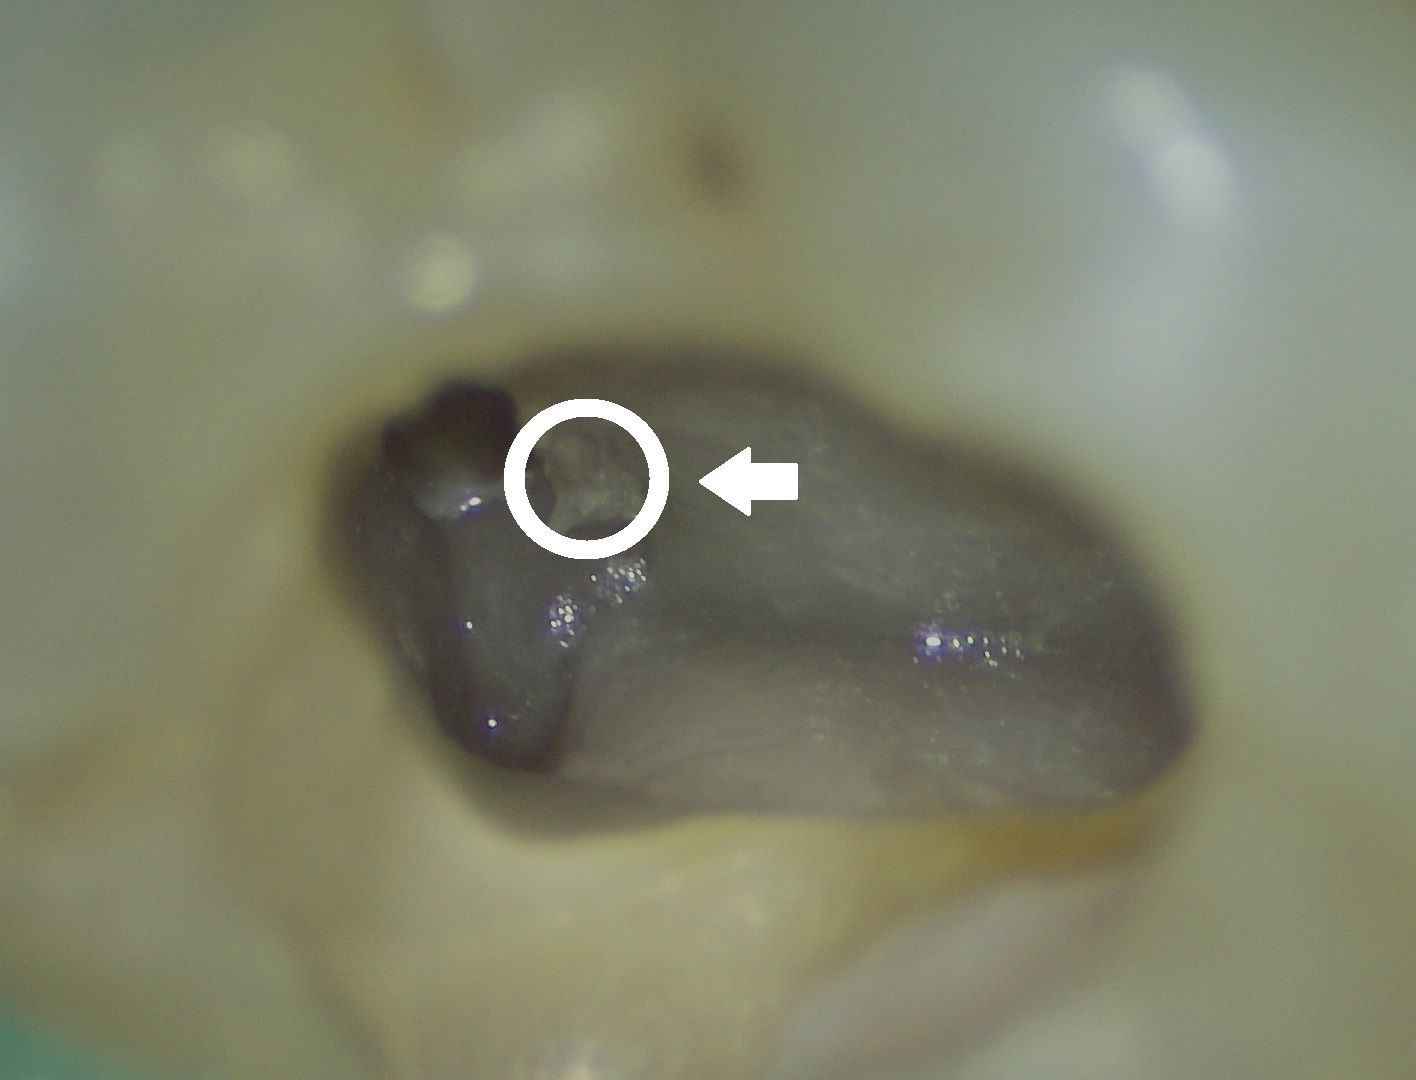

↑在肉眼情況下最常被遺漏的根管